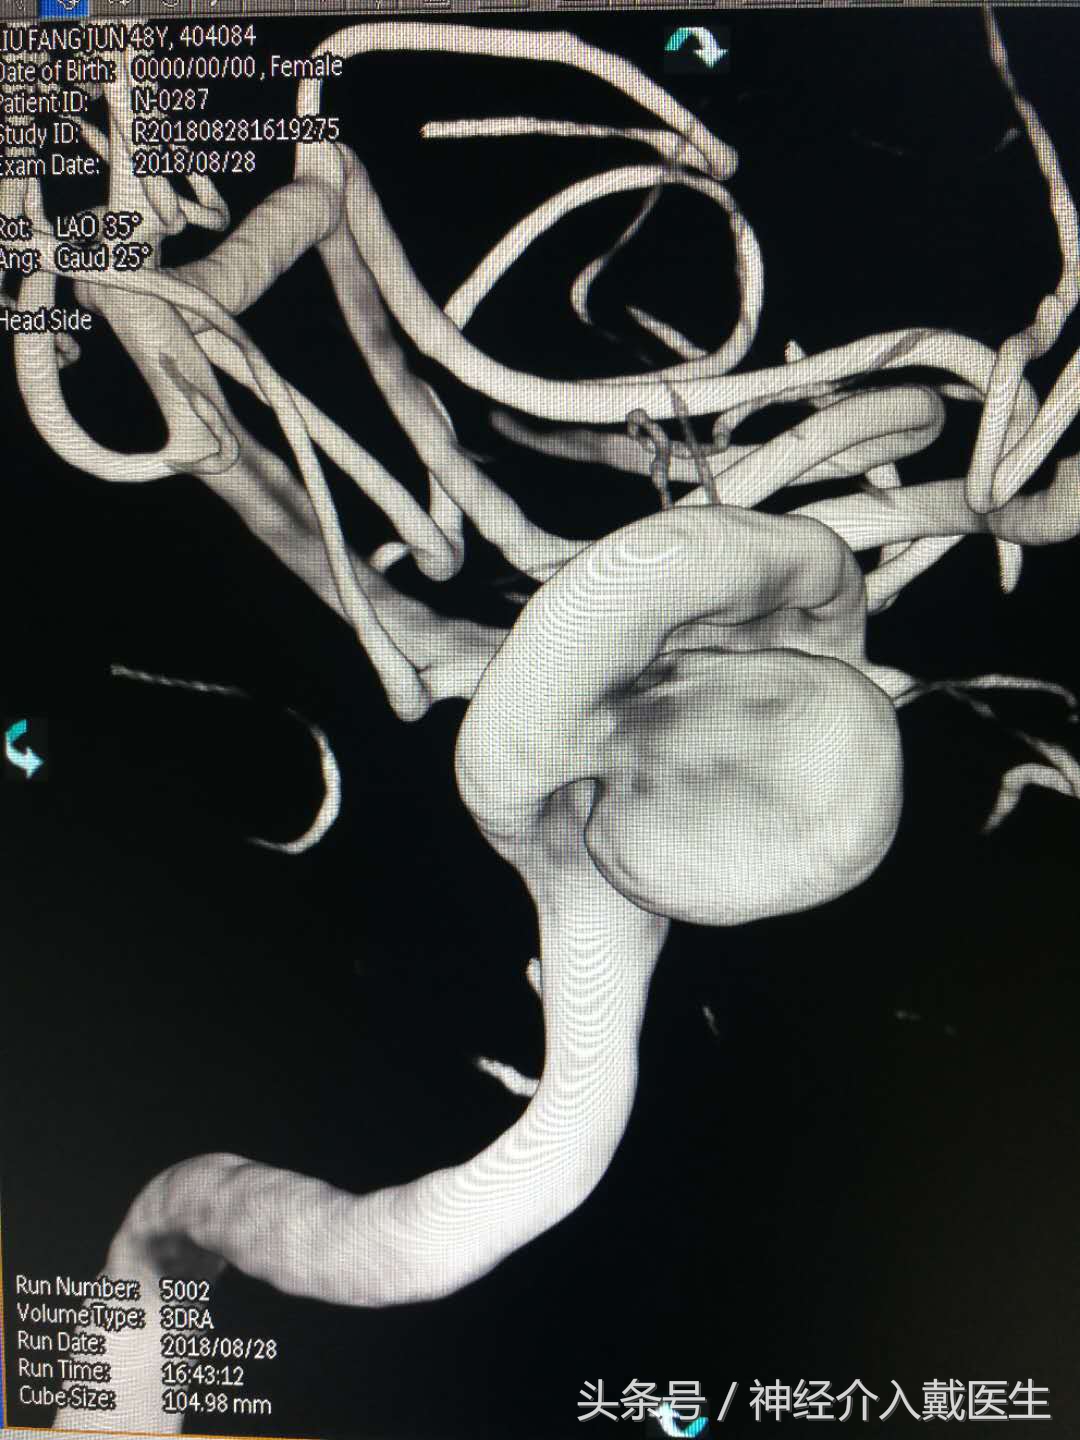

这是一个大型的颈内动脉海绵窦动脉瘤。治疗过程并不复杂。

刘某某,女,48岁。因右侧颈部异常跳动,加重伴视物模糊2年入院,头部核磁共振血管成像提示右侧颈内动脉动脉瘤。

脑血管造影进一步明确右侧颈内动脉海绵窦大型动脉瘤,直径超过10mm,

3D图像显示瘤体,瘤颈,载瘤动脉关系,长度。